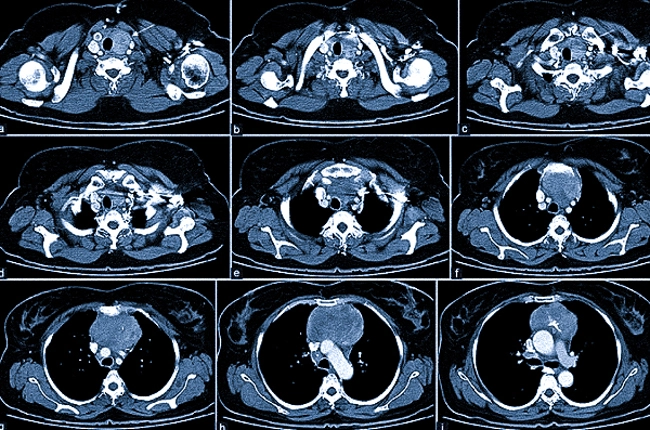

Контрастная МРТ применяется для диагностики сосудистых заболеваний и новообразований матки и яичников. Перед обследованием пациентке устанавливается внутривенный катетер, после чего выполняются несколько снимков без контраста. Затем процедура приостанавливается, и с помощью автоматизированного устройства вводится раствор гадолиния, который визуализирует сосудистую сеть, тем самым позволяя увидеть мельчайшие изменения в структуре матки и яичников.

МРТ органов малого таза с контрастным усилением

Сканирование продолжается через 10 минут после того, как был введен контрастный раствор.